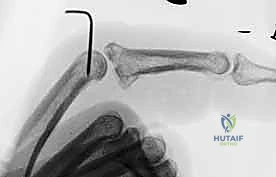

3. Confirming the Blocking Effect and Stability

This is a critical step, fellows. The pin must effectively block hyperextension without restricting necessary flexion.

• Test Extension Block: Gently extend the PIP joint. The middle phalanx should come to a hard stop against the K-wire, preventing full extension and dorsal subluxation. The exact angle of allowed extension will depend on the stability required, typically allowing 20-30 degrees of extension.

• Test Flexion: Gently flex the PIP joint. It should be able to flex fully to 90 degrees or more without impingement from the K-wire. If flexion is restricted, your pin is likely too long or is tethering the extensor mechanism.

• Fluoroscopic Verification: Confirm the blocking effect and joint congruity in all ranges of motion under fluoroscopy.

Image

Clinical image of K-wire in place, demonstrating allowed flexion.

Clinical image of K-wire in place, demonstrating blocked extension.